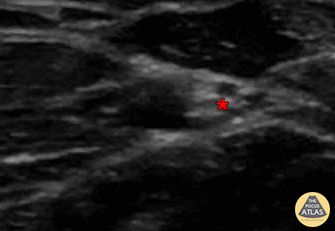

In-plane ulnar nerve block, with needle seen entering from screen right (ulnar aspect), with anesthetic deposited superficial/adjacent to ulnar nerve (*). The ulnar artery can be seen pulsating screen left of (radial to) the nerve. Denver Health Ultrasound Fellowship Archive